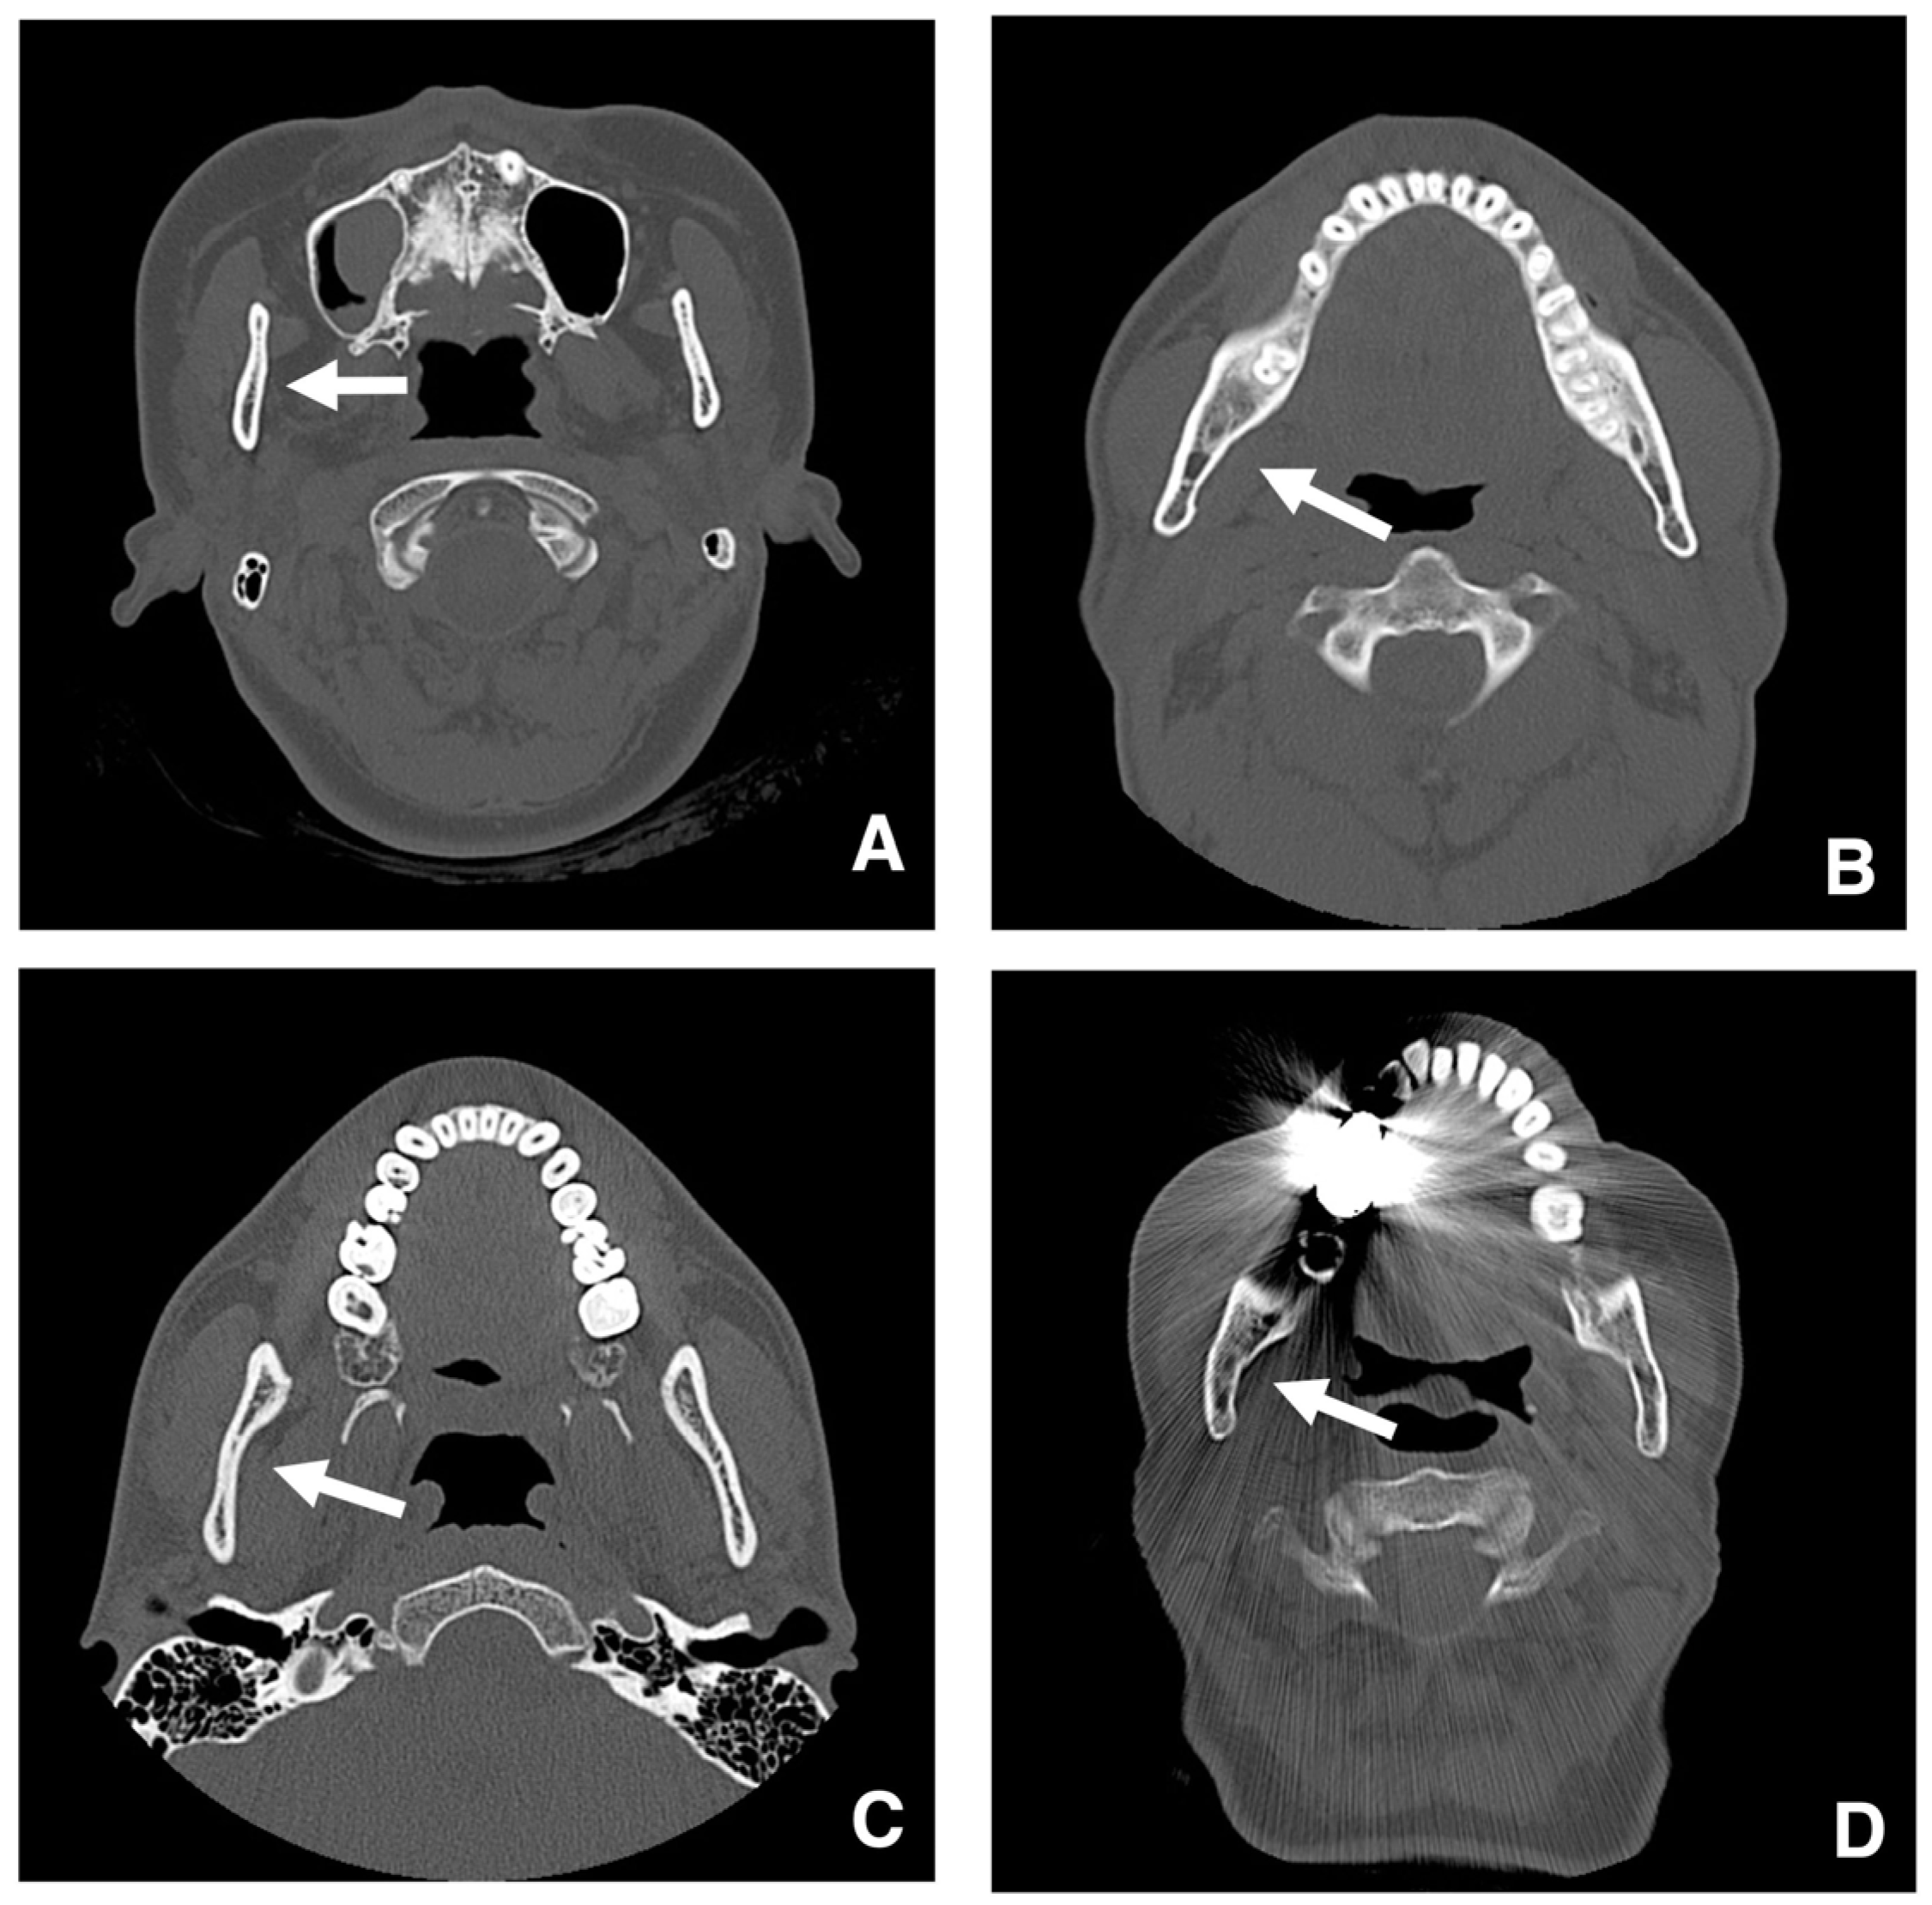

| Improving safety through prediction of surgical difficulty and complication 1. Circumstance of pterygoid venous plexus Carefully observe the fat tissue surrounding the medial and lateral pterygoid muscles to assess the development of the internal vascular structures (using CT and MR to evaluate the size of the fat tissue) 2. Fusion status of the maxillary tuberosity and pterygomaxillary suture When the fusion is narrow and the degree of calcification (CT number) is low or when the fusion is wide and high 3. Course of the descending palatine artery and thickness of surrounding bone When the palatal canal wall is thick, the probability of damage during transection is low. When it is thin, the possibility of damage cannot be ruled out. Setting the osteotomy line 1. Distance from the piriform rim to the greater palatine canal Long, short, cortical bone thickness, presence or absence of bone irregularities 2. Evaluation of the size, morphology, and internal features (mucosa, septa, etc.) of the maxillary sinus Size, shape, presence or absence of septa, presence or absence of masses, presence or absence of mucosal thickening 3. Relationship between the floor of the maxillary sinus and the apices of the molars Describe the maxillary sinus floor and the apex of each molar tooth 4. Presence of nasal septal deviation, size of the nasal passages, and thickness of the lateral nasal wall bone Presence or absence of nasal septal deviation, Size of the nasal passage, Thickness of the cortical bone of the lateral wall 5. Course of the mandibular artery The course from the pterygoid cleft to the pterygopalatine fossa in the posterior maxilla |